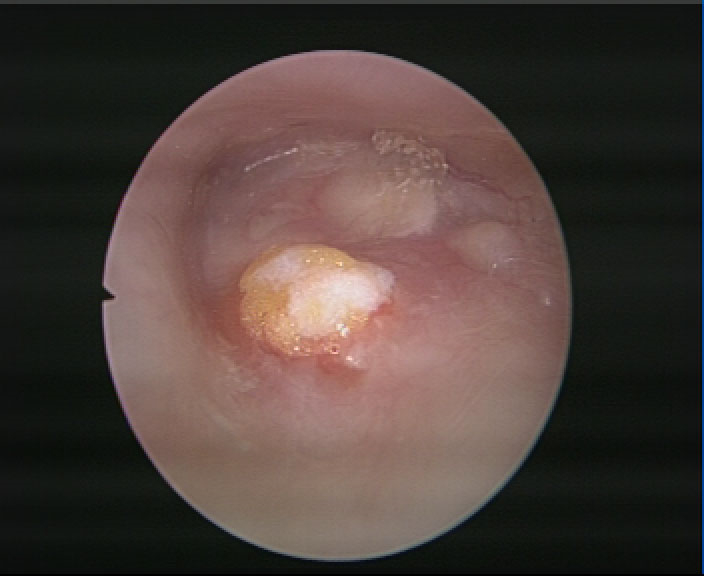

中耳炎鼓膜穿孔